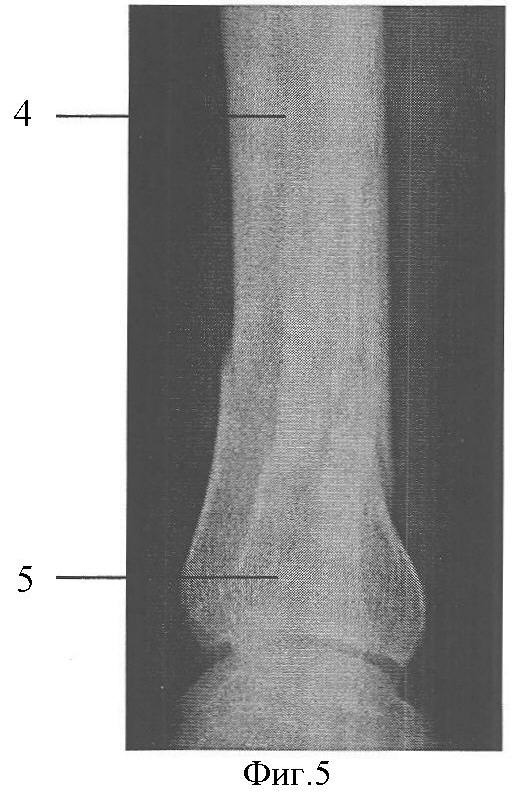

Фиг.4. Исходная рентгенограмма в прямой проекции.

Фиг.5. Исходная рентгенограмма в боковой проекции.

Клинический пример: Пациентка А., 43 лет. Диагноз: Закрытый перелом дистальных метафизов обеих костей правой голени (фиг.4, 5). Произведена операция (фиг.8, 9), при этом после внедрения стержня 2 интрамедуллярно под контролем электронно-оптического преобразователя проведены репозиционно-блокирующие винты 3 через костные отломки 4, 5 и резьбовые отверстия 1 в стержне 2, при установке винтов 3 (фиг.3, 6, 7) достигнута компрессия отломков 4, 5 с устранением остаточных их смещений за счет притягивания отломков 4, 5 к стержню 2 головками винтов 3 и достигнута окончательная репозиция и полиаксиальная жесткая стабилизация отломков 4, 5, исключающих возможность смещений отломков 4,5 после установки металлоконструкции и в послеоперационном периоде. Винты 3 выполнили как репонирующую, так и блокирующую роль. Полная нагрузка на ногу после операции (фиг.10). Срок нетрудоспособности 4 недели.